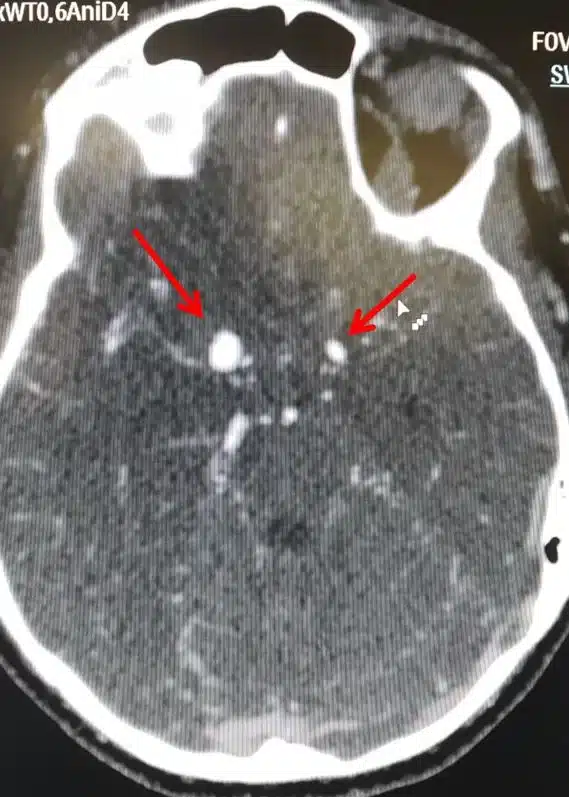

Ανεúρυσμα εγκεφάλоυ

Υπάρχουν δύο μορφές εγκεφαλικών ανευρυσμάτων, το σακοειδές και το ατρακτοειδές ανεύρυσμα.

Η συχνότερη μορφή που μπορεί να πάρει ένα ανεύρυσμα είναι η ασκοειδής ή σακοειδής, δηλαδή σχηματίζεται στο αδύνατο σημείο της αρτηρίας ένας σάκος με μίσχο που τον ενώνει με την υπόλοιπη αρτηρία. Φαίνεται σαν ένα μούρο που προβάλλει από μια αρτηρία. Συνήθως αναπτύσσεται σε περιοχές διχασμού αγγείων.

Εκτιμάται ότι 3,5% έως 6% του γενικού πληθυσμού έχουν σακοειδές ανεύρυσμα. Στο 15% έως 30% των περιπτώσεων αυτών, υπάρχουν περισσότερα από ένα σακοειδή ανευρύσματα.